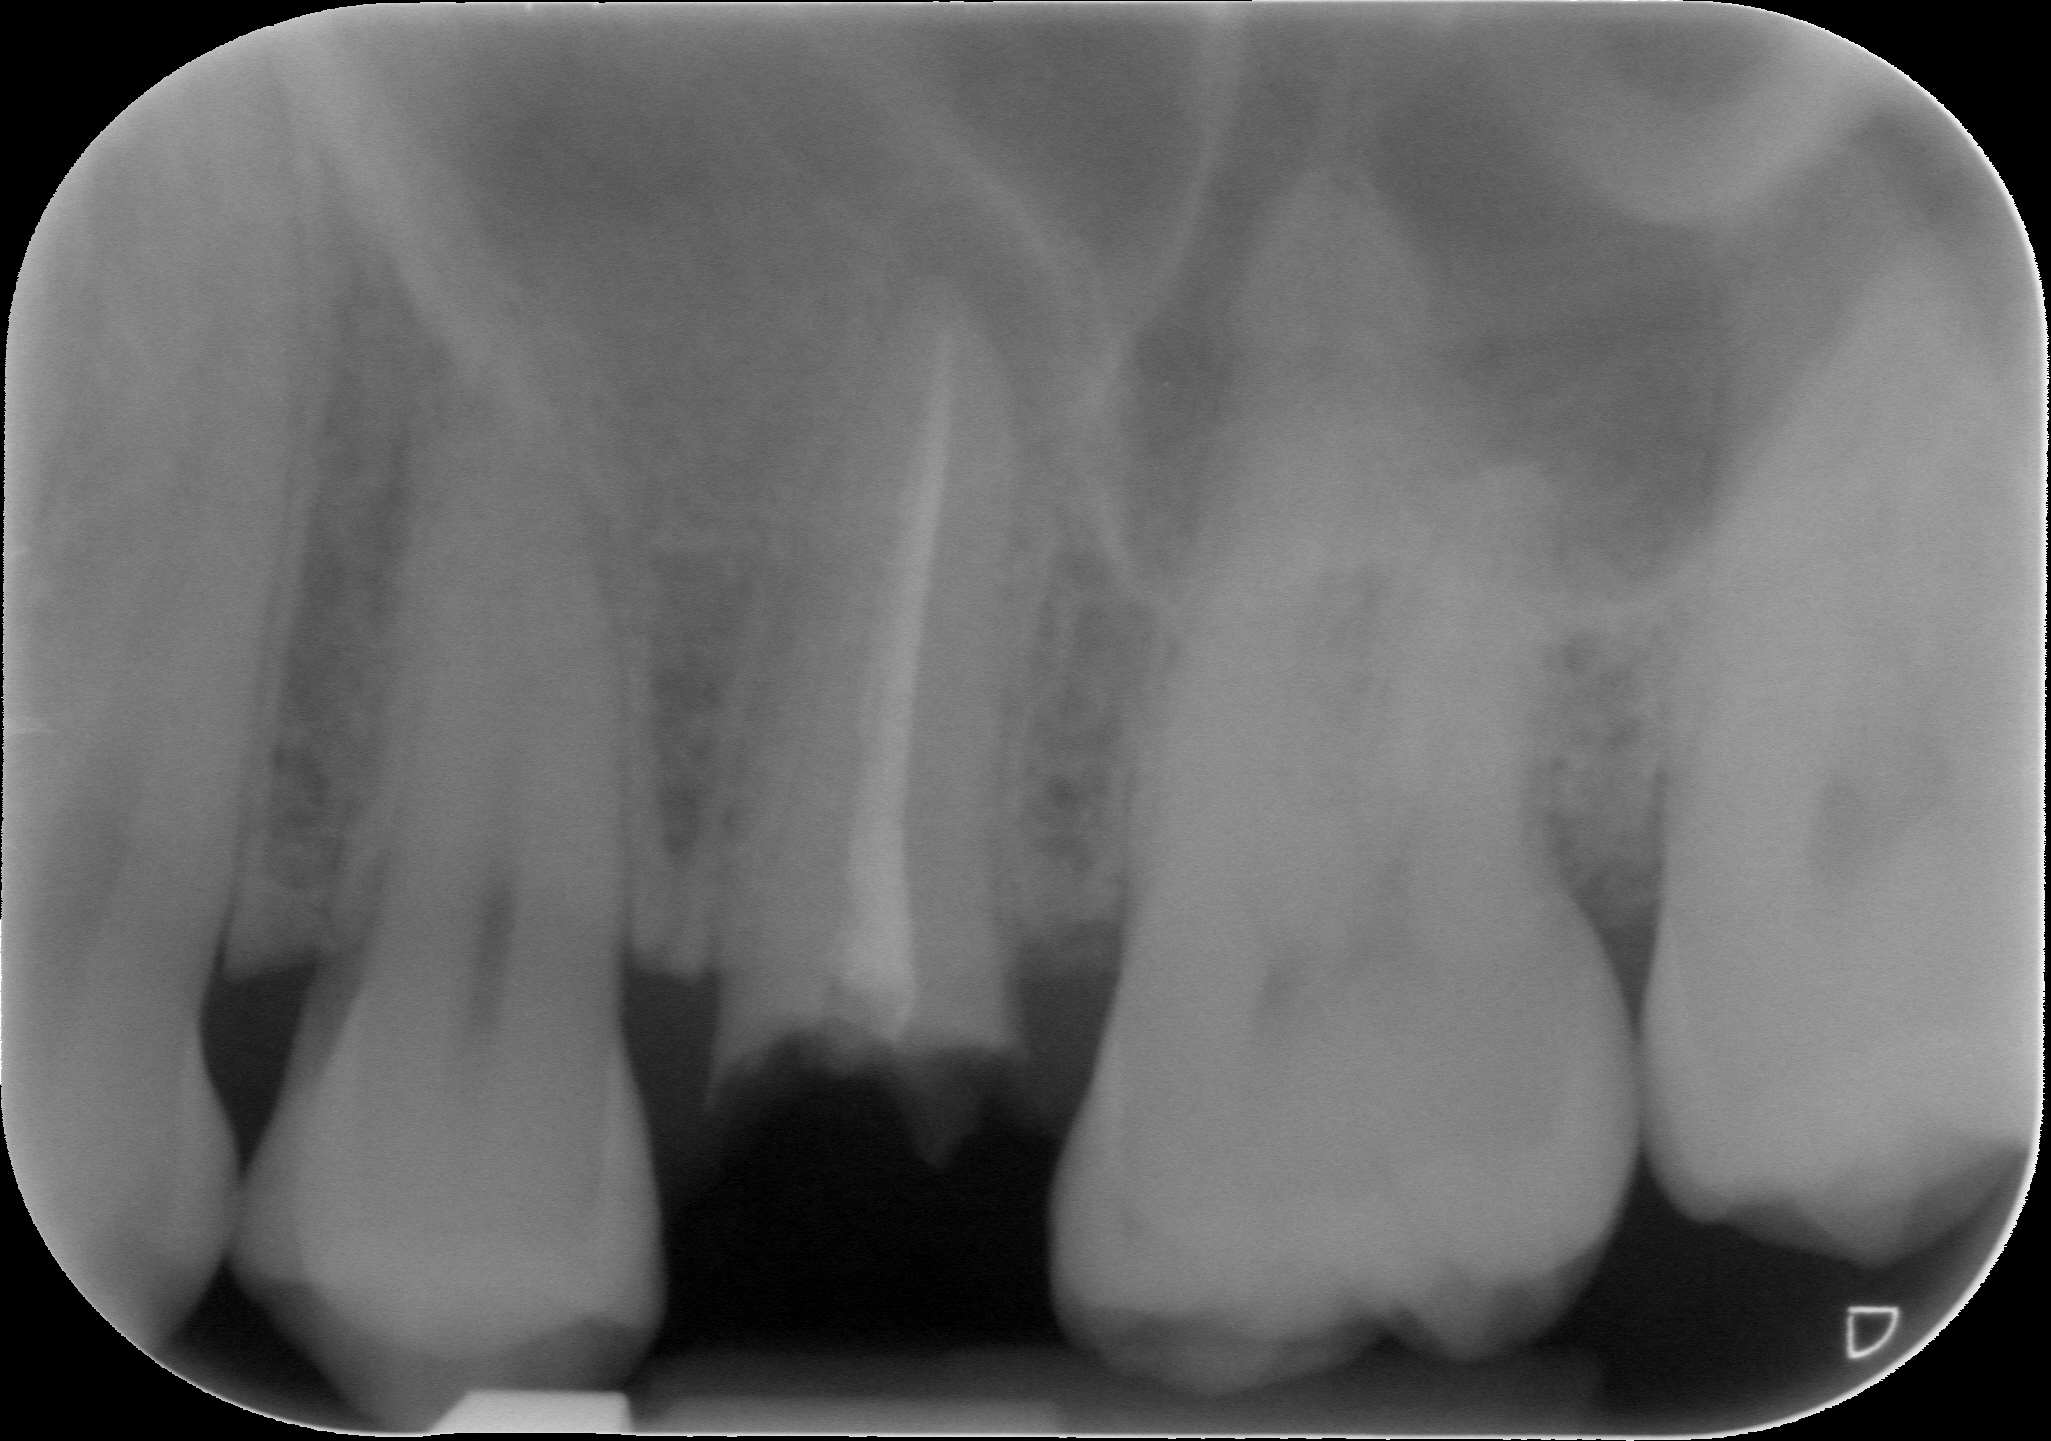

Mi hanno diagnosticato una parodontite avanzata grave

Buongiorno, innanzitutto vi ringrazio per il servizio che mettete a disposizione dei pazienti " virtuali". Ho 39 anni e da un paio di mesi mi hanno diagnosticato una parodontite avanzata grave, con tasche di 4/5 millimetri nell'arcata inferiore e maggiori nell' arcata superiore, soprattutto negli incisivi che sono uno di 6 e l